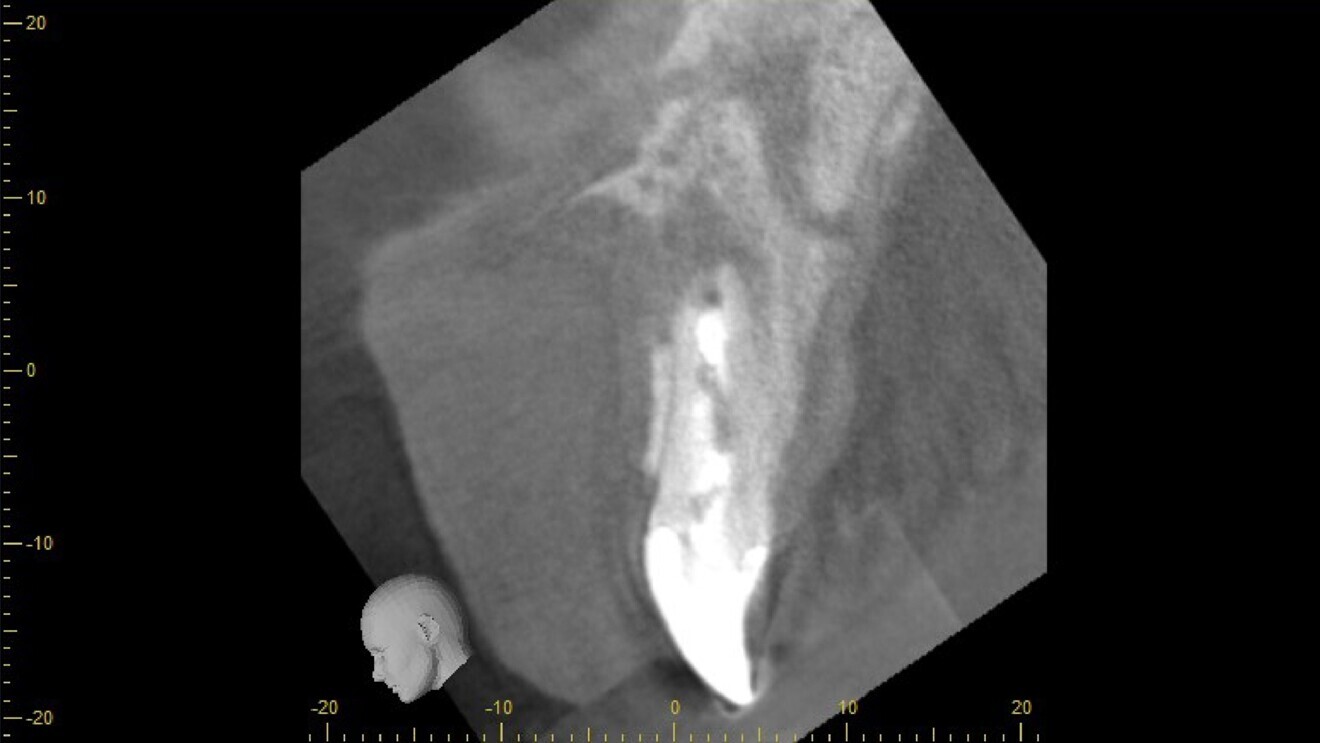

Tooth #11 was immobile and associated with adequate ridge width and a wide band of keratinised tissue (Fig. 1). There was also a favourable Class I incisor relationship and adequate space to accommodate an implant-supported restoration. A CBCT scan of the site revealed an inadequately endodontically treated tooth with a lack of an apical seal and incomplete obturation of the canal. The tooth benefited from good bone support provided by a robust facial bone plate at the alveolar crest (Fig. 2), but there was a large periapical dentigerous cyst measuring approximately 10 × 8 mm, extending to the mesial surface of tooth #12, and complete fenestration of the facial plate superiorly (Fig. 3). The prognosis of the tooth was deemed to be hopeless, and extraction was indicated.

Fig. 3: Cystic cavity measuring approximately 10 × 8 mm.